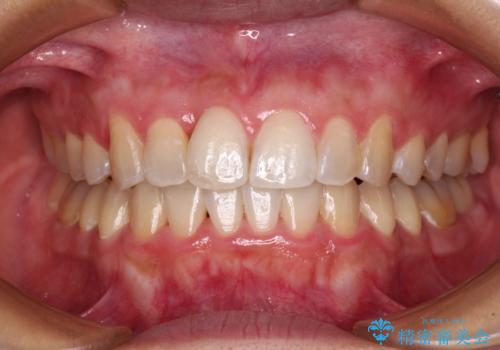

- 地元の歯科医院にて前歯4歯を仮歯に替えたものの、汚れていることが気になるとのことで来院された患者様です。

不適な仮歯の影響で歯肉が腫れていたため、新しい仮歯に替えた後に歯肉の腫れが引くのを待ち、オールセラミッククラウンにて補綴することとしました。

仮歯を変えたことで歯肉の腫れは引き、根管治療も功を奏して膿の出口はきれいに消退しました。